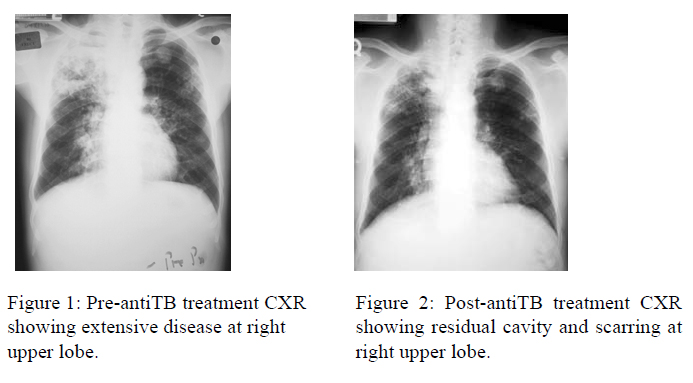

He had history of diabetes mellitus and hypertension for 5 years. He was treated with metformin 1g BD, gliclazide 160mg BD and lisinopril 7.5mg QD. Both conditions were well-controlled. He had history of pulmonary tuberculosis in 2004 which was sputum culture positive with favourable drug susceptibility pattern. The main bulk of disease was at the right upper lobe. He was treated with 9 months of anti-TB treatment with good response except residual cavity and scarring at the right upper lobe (fig 1 and 2)